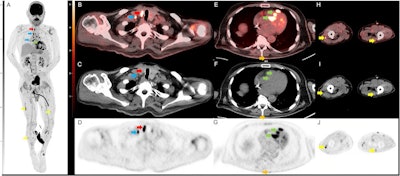

Selected images from the initial FDG-PET/CT. Coronal FDG PET maximum intensity projection (MIP; A) demonstrates multifocal FDG avid foci including a right thyroid nodule (red arrow), multiple supraclavicular, mediastinal, hilar, and mesenteric lymph nodes (blue arrow), multifocal nodular cardiac uptake (green arrow), and multiple nodular soft tissue deposits in the intramuscular fascia and skin (yellow arrow). Transaxial FDG-PET/CT (B) CT (C) and PET (D) images show a hypermetabolic nodule along the right thyroid gland which was a pathology proven to be sarcoidosis. Adjacent hypermetabolic right supraclavicular lymph node (blue arrow) was also noted and likely nodal sarcoid involvement. Transaxial FDG-PET/CT (E) CT (F) and PET (G) images through the thorax demonstrate nodular intense FDG uptake along the cardiac intraventricular septum (green arrow) and a nodular focus of cutaneous uptake along the back (orange arrow) which was found to be inflamed seborrheic keratoses. Transaxial FDG-PET/CT (H) CT (I) and PET (J) images through the legs demonstrate multinodular hypermetabolic focal (yellow arrow) along the intramuscular fascia and subcutaneous fat, which is also likely related to the patient sarcoid. Image courtesy of Radiology Case Reports through CC BY 4.0.In this case, a 65-year-old man initially presented with slow, shuffling gait, and over four months became bed- and wheelchair-bound with bowel and bladder incontinence and alogia. He was presumed to have rapidly progressive dementia due to Creutzfeldt-Jakob disease based on an "outside interpretation" of a brain MRI, was placed in hospice, and was given less than six months to live, the authors noted.

The whole-body FDG-PET/CT scan demonstrated multiple markedly hypermetabolic lymph nodes throughout the body, including a hypermetabolic 2 cm by 1.4 cm thyroid nodule, as well as marked global hypometabolism in the brain. A subsequent biopsy of the lymph nodes was nondiagnostic, but a thyroid biopsy tissue yielded a diagnosis of sarcoid, according to the report.

"This result, coupled with the PET/CT findings, suggested the diagnosis of sarcoid with neurologic, thyroid, and likely cardiac involvement," the group wrote.